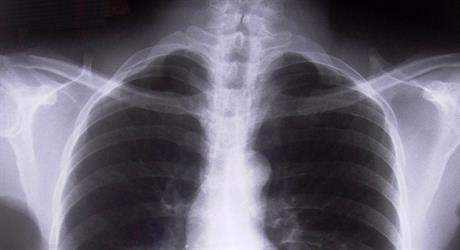

Kakvi su nam srce i pluća?

Zdravstveno stanje stanovnika Primorsko-goranske županije